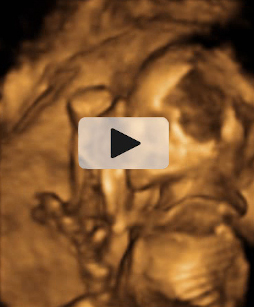

Las ecografías en 2D y en 3D en la semana 20 de embarazo permite diagnosticar algunas malformaciones congénitas fetales, como el labio leporino, que se visualiza en estas imágenes.

Labio leporino (*)

Visualización del mismo caso con ecografía 2D (izquierda) y con ecografía 3D (derecha). La imagen más evidente en la ecografía 3D hace más comprensible para los padres el alcance del problema.

Ecografía Embarazo 4D Semana 20 - MALFORMACIONES FETALES